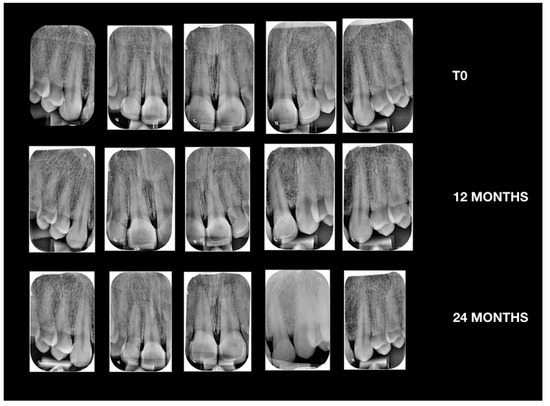

Case Report